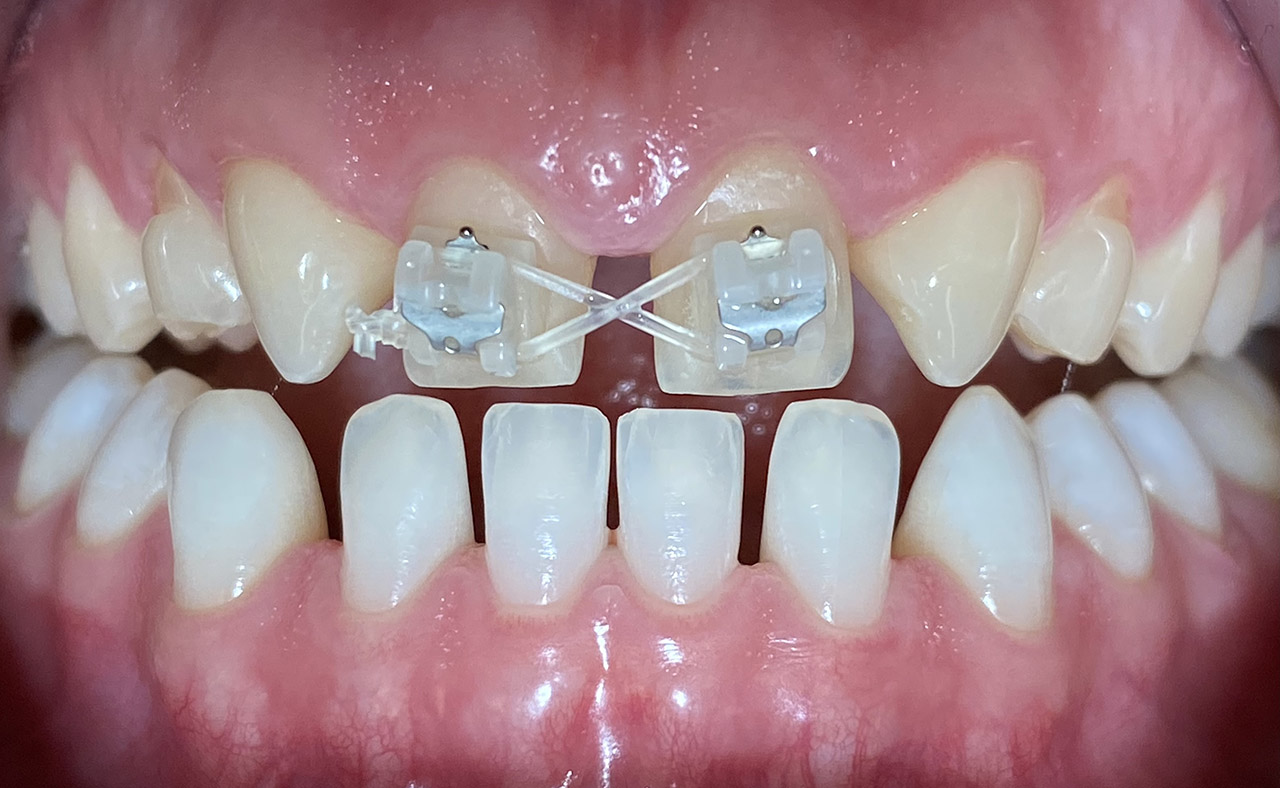

Klebebrücken bei Zahnaplasie (Nichtanlage):

Vorbehandlung (Dr. Ernst Köle): Kieferorthopädischer ”Platzhalter mit provisorischem Zahn”.

Minimalinvasive Therapie: 2 keramikverblendete Klebebrücken (“Zirkonflügerl") adhäsiv zementiert.

Konservativ ohne Knochenaufbau und Schleimhauttransplantat.